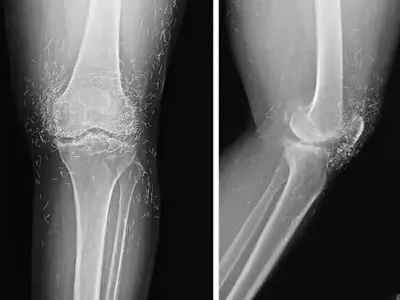

کشف صدها رشته طلای خالص در زانوی زن مبتلا به آرتروز

پزشکان کره جنوبی، صدها رشته نازک از طلای خالص در زانوهای زن ۶۵ساله مبتلا به آرتروز پیدا کردند.